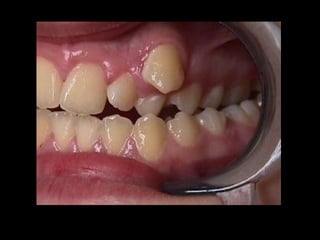

Información clínica loco-regional:

1. Grado de movilidad del diente que se

va a extraer.

2. Morfología de la corona y su estado.

3. Grosor de la cortical ósea.

4. Estado de los dientes vecinos y su

relación con el diente que se va a extraer.

5. Estado de la mucosa oral.